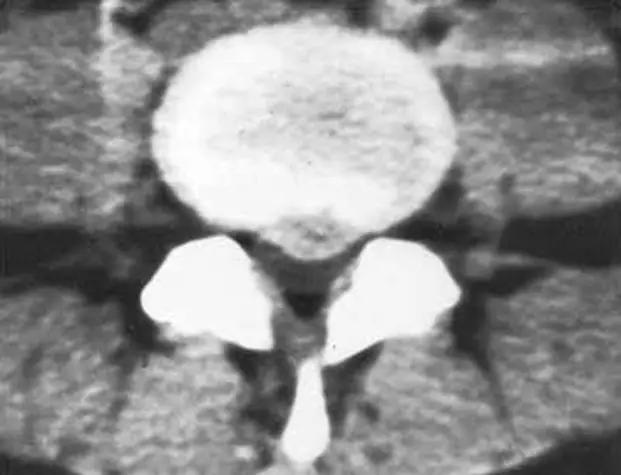

正常椎间盘CT图像

椎间盘突出图像

椎间盘突出(中央型)

中央型